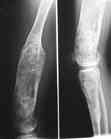

Деформация правой нижней конечности с 6 месяцев (стала прогрессировать после года, с момента начала ходьбы). Поставлен диагноз болезнь Олье, варусная деформация, укорочение правой нижней конечности на 4,5 см. 1993 г. - операция остеоклазия на уровне очагов поражения в н/3 правой бедренной кости и в/3 правой большеберцовой кости с одномоментной коррекцией деформации и фиксацией костных фрагментов спицами Киршнера.После начала статической нагрузки (1994 г.) появился рецидив деформации и укорочения. Вторая операция - ЧКО АВФ, аппарат демонтирован через 2недели в связи с развившимся на уровне стержня переломом, после чего находилась в гипсовой повязке до консолидации костных фрагментов. Далеелечилась консервативно в гипсовой повязке. Выраженная деформация и укорочение правой нижней конечности. Относительная длина бедер: справа -34 см, слева - 51 см; анатомическая длина голеней: справа - 29 см, слева - 39 см. Величина варусной деформации на уровне дистального отдела правого бедра составляет - 80 град. Амплитуда движений в коленных суставах (разгибание/сгибание ): справа - 0/0/100 град.; слева - 0/0/30 град. Отмечается боковая и ротационная нестабильность на уровне правого коленного сустава. Амплитуда движений в голеностопных суставах - в норме. Тактика лечения? Заранее благодарю! С уважением,А.В.Владзимирский

Высылаю вам фото подобной больной, у нее тоже первая попытка до меня была безуспешной.

Нужен аппарат Илизарова стабильный с множеством спиц с напайкой, временной фиксацией колена аппаратом на голени. Наверное, проще первый раз начать с бедра, остеотомию выполнить прямо на уровне перехода очага в дистальный метафиз бедра. Дистракционный остеогенез вызовет перестройку хрящевой ткани в костную. Понадобится еще пара этапов.